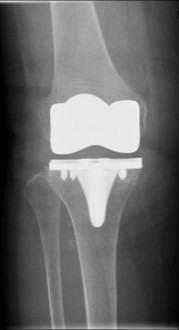

変形性膝関節症、膝関節骨軟骨障害

加齢性変化による疾患では変形性膝関節症が多く、単顆型を含めた人工膝関節置換術はもちろん、適応があれば骨を温存することのできる膝周囲(大腿骨遠位・高位脛骨)骨切り術も行っています。若年者の軟骨損傷に対しては損傷の程度に応じて骨軟骨柱移植術・骨軟骨片固定術・培養軟骨移植術を行っています。

人工膝関節置換術